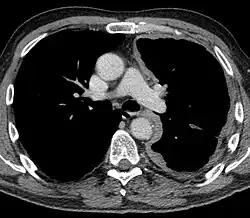

Die Diagnose wird meist erst in einem fortgeschrittenen Stadium gestellt. Zur Diagnosesicherung wird ein Röntgen, CT oder MRT der Lunge und eine Bronchoskopie zur differenzialdiagnostischen Abgrenzung eines Bronchialkarzinoms durchgeführt. Bei der Pleurapunktion können in 30–50 % der Fälle Tumorzellen nachgewiesen werden; zu beachten ist hierbei das etwa 20%ige Risiko der Bildung von Metastasen im Stichkanal durch die direkte Verschleppung von Tumorzellen (= Impfmetastasen). Eine Pleurapunktion alleine ohne Nachweis von Tumorzellen schließt ein Pleuramesotheliom nicht aus. Die höchste Aussagekraft besitzt die Thorakoskopie mit Biopsie, welche in Zweifelsfällen durchgeführt werden muss.